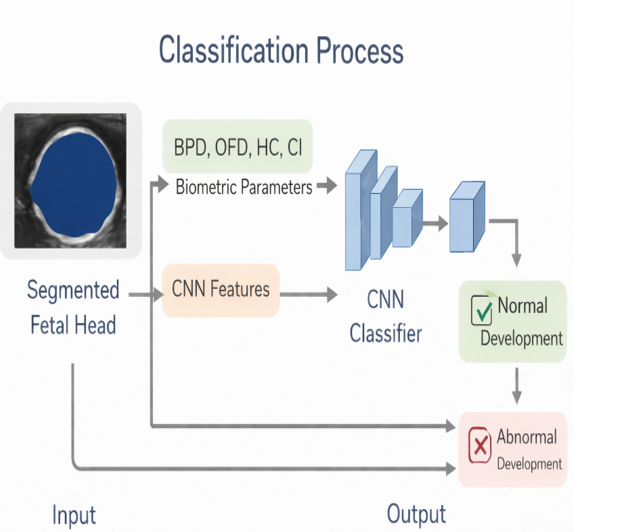

CLASSIFICATION

• The classification module is used to determine whether the fetal head development is Normal or Abnormal.

• The system combines biometric parameters (BPD, OFD, HC and Cephalic Index) with CNN-based image features for better decision accuracy.

• These features are given as input to a Convolutional Neural Network (CNN) classifier.

• The CNN learns growth patterns and deviations in fetal head structure and measurements.

• Based on learned features, the model classifies the fetal head into Normal Development or Abnormal Development.

Purpose of Classification

✓ Supports early prenatal screening

✓ Reduces manual interpretation dependency